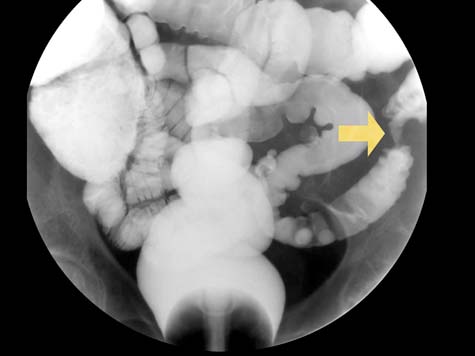

CT (CAT) scan showing a segment of abrupt narrowing within the colon (arrow) giving the classic 'apple core' appearance suspicious for colon cancer.

Note: Images are shown for illustrative purposes. Do not attempt to draw conclusions or make diagnoses by comparing these images to other medical images, particularly your own. Only qualified physicians should interpret images; the radiologist is the physician expert trained in medical imaging.